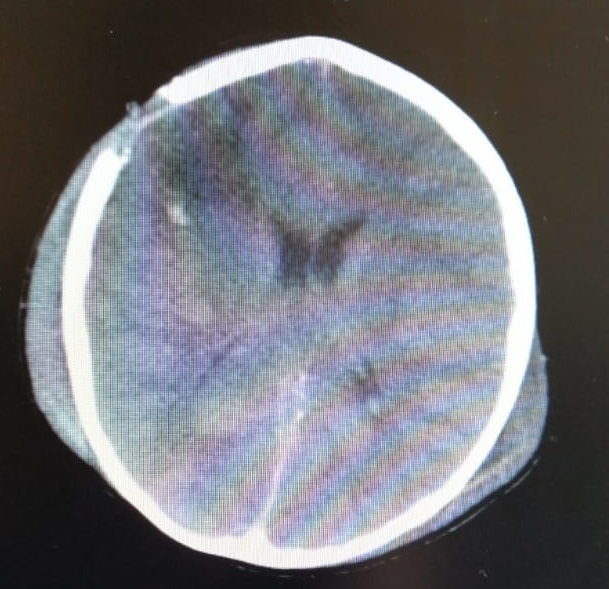

“El niño llega en malas condiciones, con apoyo respiratorio mecánico, se encontraba bajo sedación con medicamentos y al examinarlo encontramos que tenía dos heridas en el cráneo, entrada y salida del proyectil”; explicó Julio Cesar Sánchez, Neurocirujano de la Subred Sur Occidente.

Inicialmente, los médicos realizaron un lavado y eliminación de tejido muerto bajo manejo quirúrgico, 12 horas después el menor volvió a cirugía por la presencia de sangrado y se hospitalizó en cuidados intensivos. Días después fue llevado nuevamente a cirugía por un desgarro dural (columna vertebral), el cual fue reparado y la evolución ha sido a la mejoría.

Debido a la complejidad de la cirugía, al menor se le debió retirar una parte del cráneo, donde después de tres o cuatro meses se le colocará una prótesis ósea para que pueda llevar una vida normal.